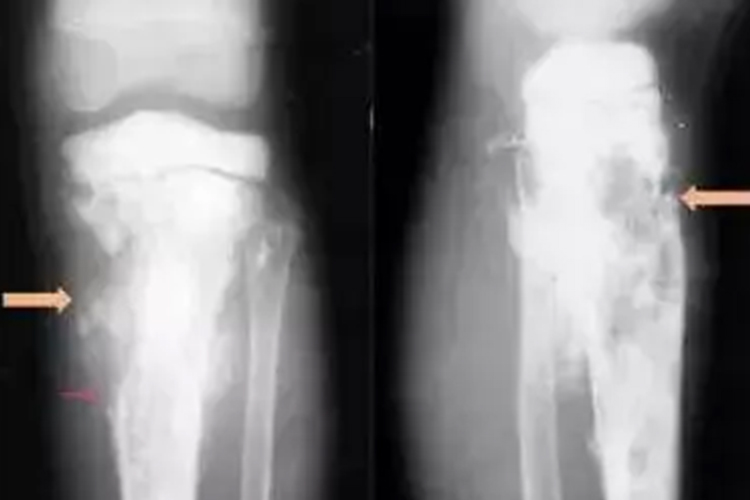

骨肉瘤:骨肉瘤患者X光可表现为不同形态,密质骨和髓腔有成骨性、溶骨性和混合性骨质破坏,骨膜反应明显,呈侵袭性发展,可见Codman三角或呈日光射线形态。

软骨肉瘤:此类患者X光常表现为千骺端的髓腔内有一单房或多房性骨密度降低或透亮区,边界不规则,其内可见斑点状或块状的钙化,部分病人肿瘤穿破新生骨形成袖口征。

骨膜肉瘤:对于骨膜肉瘤患者,骨旁可有瘤体形成,早期瘤体与骨的分界线清楚,其间可见一条透亮区,随着病变的发展,瘤体可浸润骨质,骨质破坏。瘤体常呈分叶状、圆形,瘤体内有许多新骨形成,并伴随骨小梁出现。